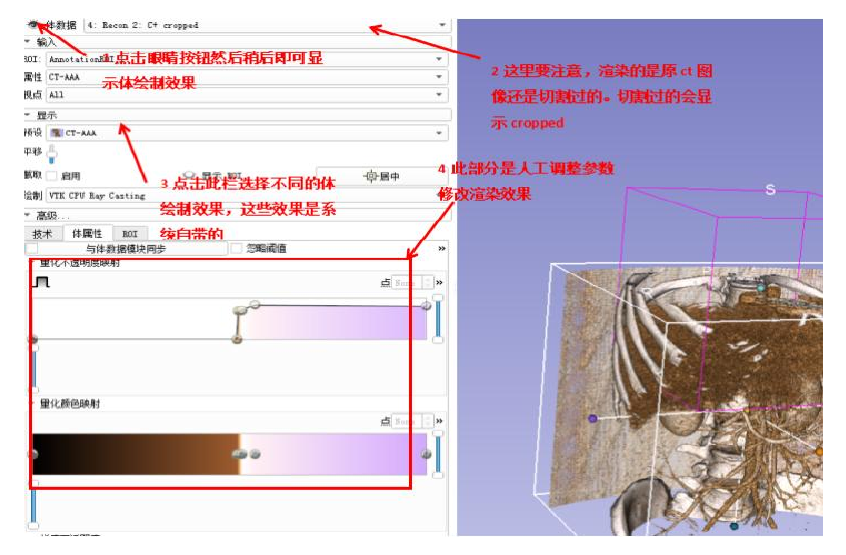

6.2.5 体绘制测试

如上图(图 7-9)所示,首先截取患者腹部区域,然后选择体绘制模块,在本系统模型视图(右图)中显示了使用光线投影算法进行体绘制运算后产生的效果。